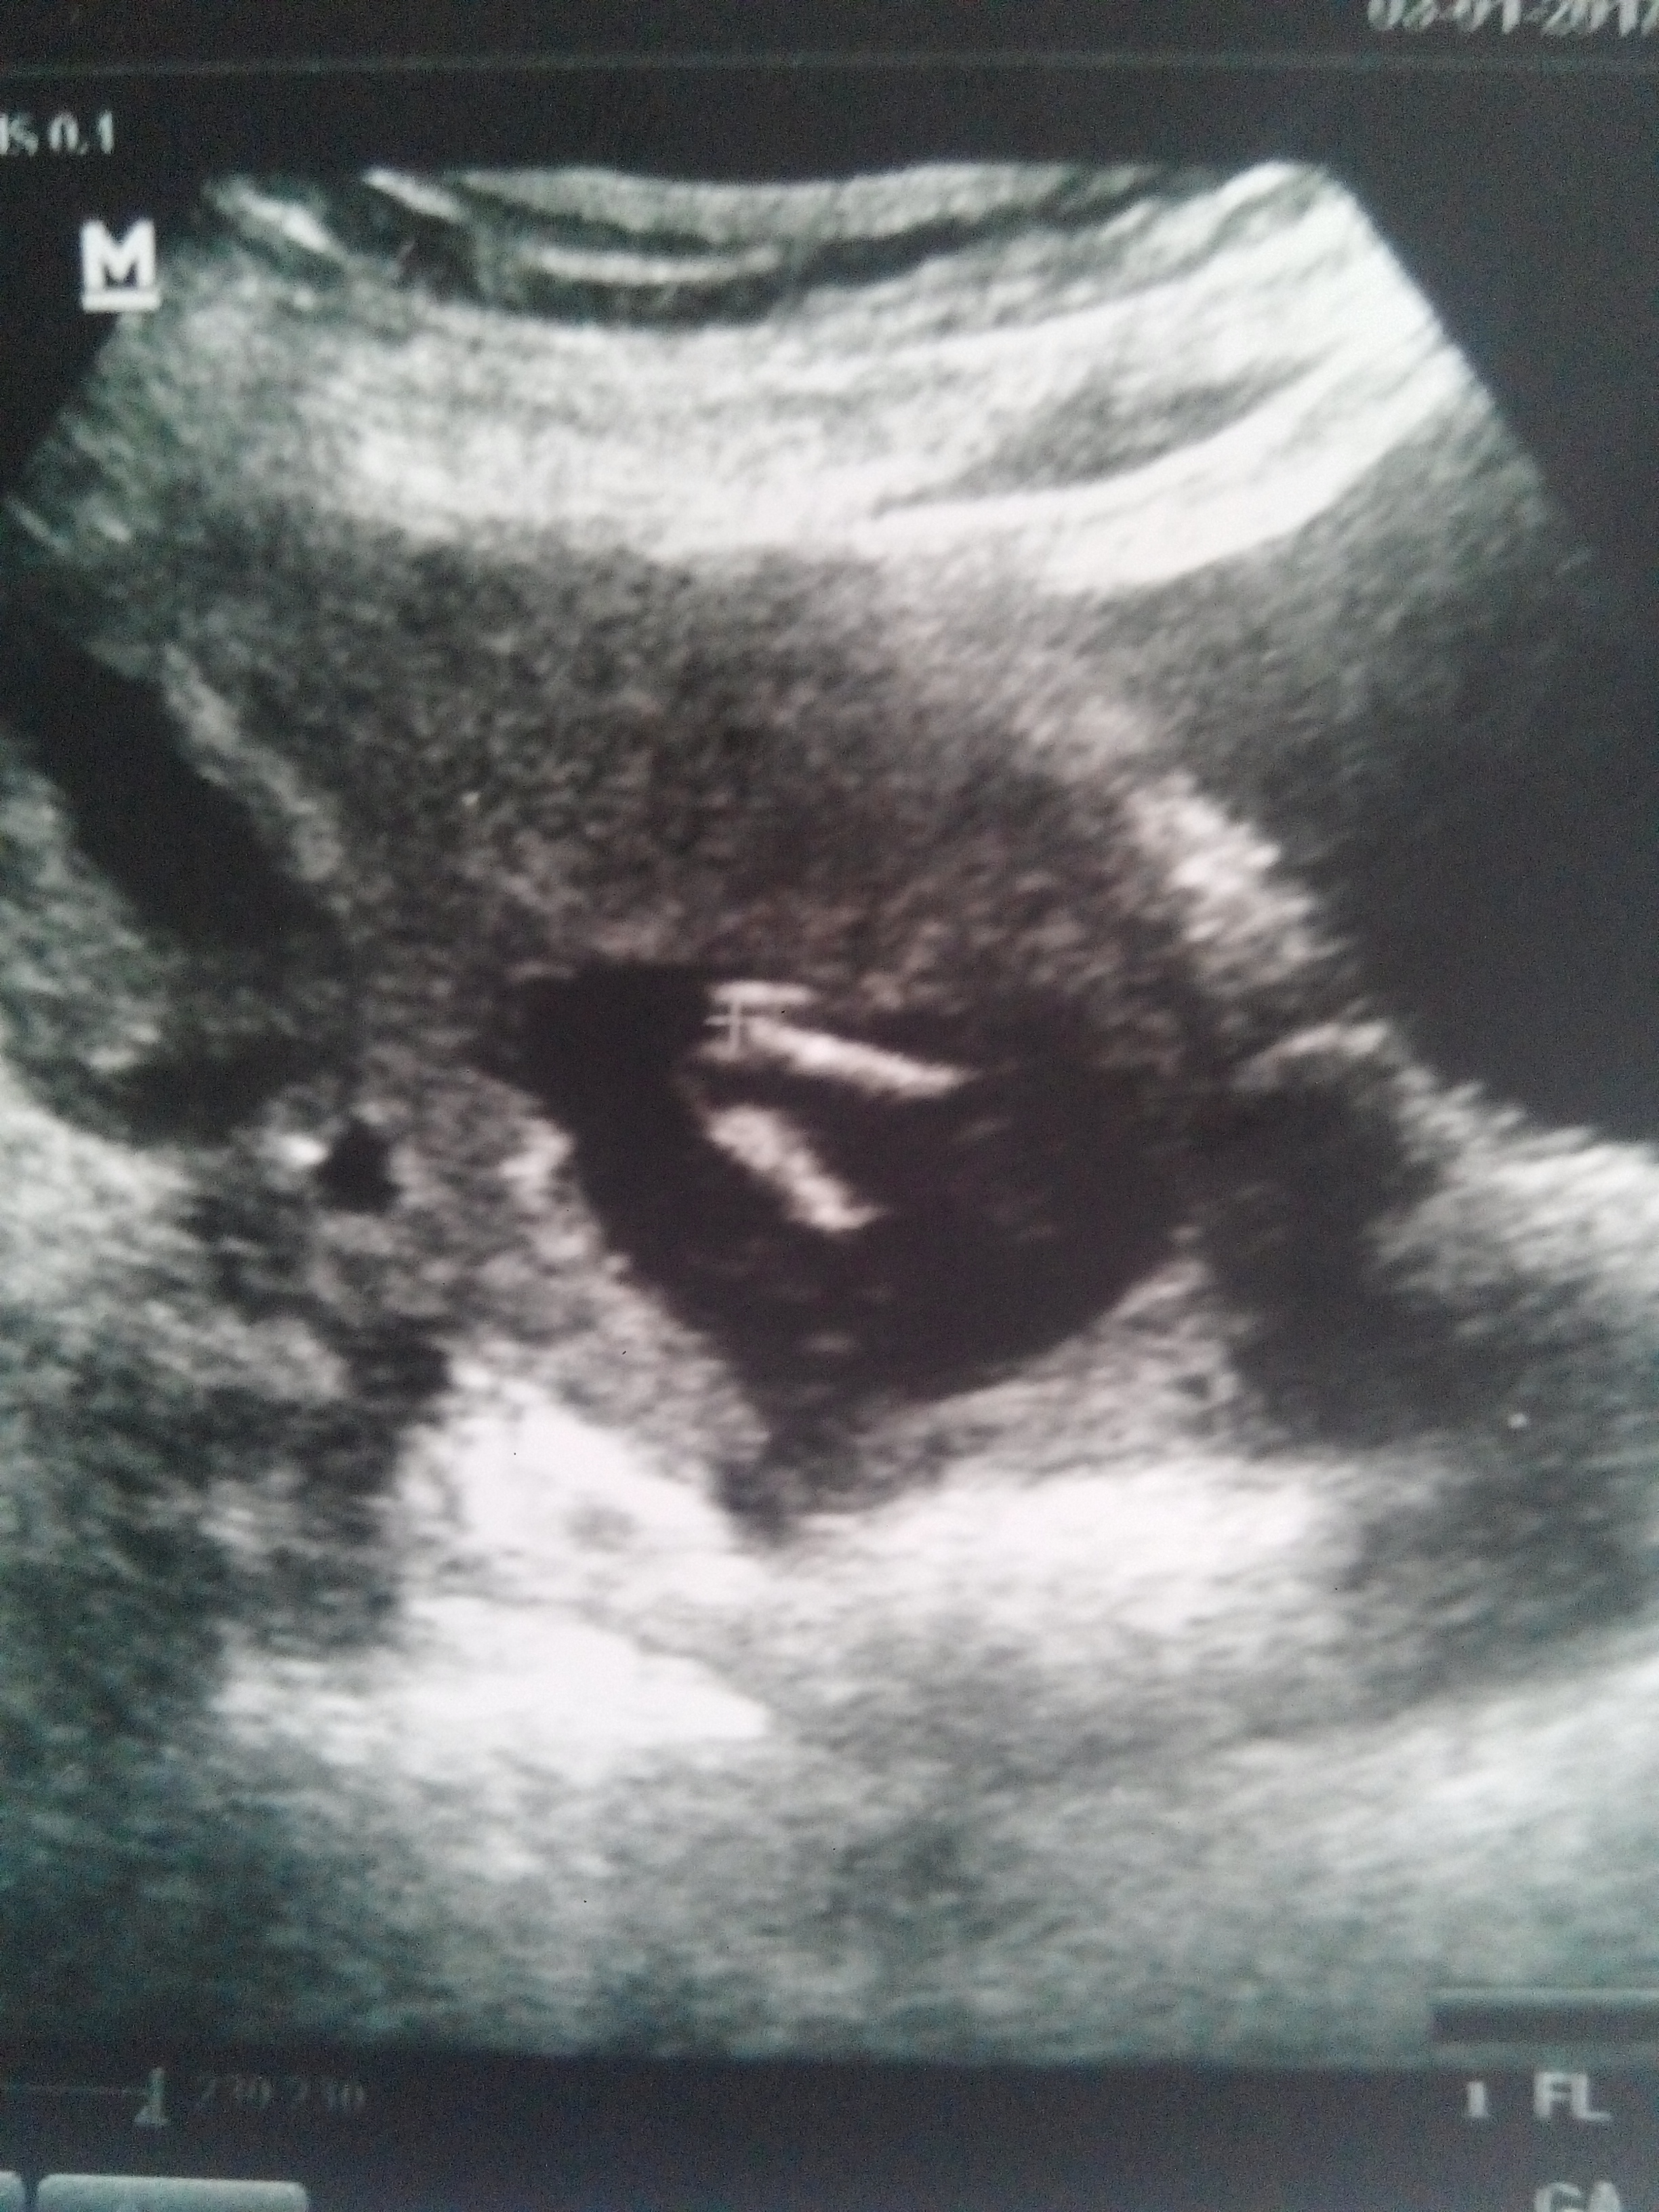

Merhabalar araniza yeni katildim 12 haftalik bebegimin fotosu üc hafta once gitmistim bende tahmin alabilir miyim 🙂

IMG-20161214-WA0022.jpeg